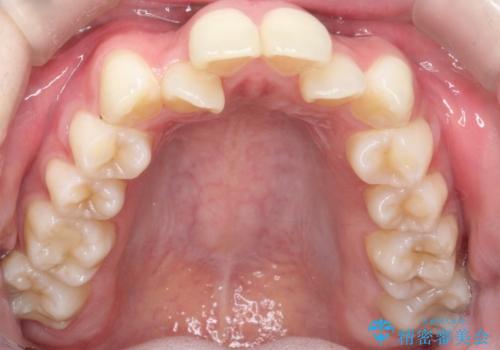

上下4本の抜歯と審美ワイヤー矯正で整った歯並びへ

- 患者様は、歯並びの乱れを整えたいとのことで来院されました。診察の結果、歯列のスペース不足が原因で前歯のガタつきが目立ち、噛み合わせにも影響が出ている状態でした。歯を正しく並べるためにはスペースの確保が必要と判断し、上下の小臼歯4本を抜歯して、審美ワイヤー矯正(白いワイヤーと透明ブラケット)で治療を行う計画を立てました。

まず、抜歯によって歯を動かすためのスペースを確保。その後、審美ワイヤー矯正を用いて、前歯のガタつきを整えながら、噛み合わせの調整も行いました。審美装置を使用することで、矯正中も目立ちにくく、自然な仕上がりを目指して治療を進めました。治療の結果、歯並びがきれいに整い、口元のバランスも改善しました。患者様からは「歯並びがきれいになり、自信を持って笑えるようになった」と喜びの声をいただきました。